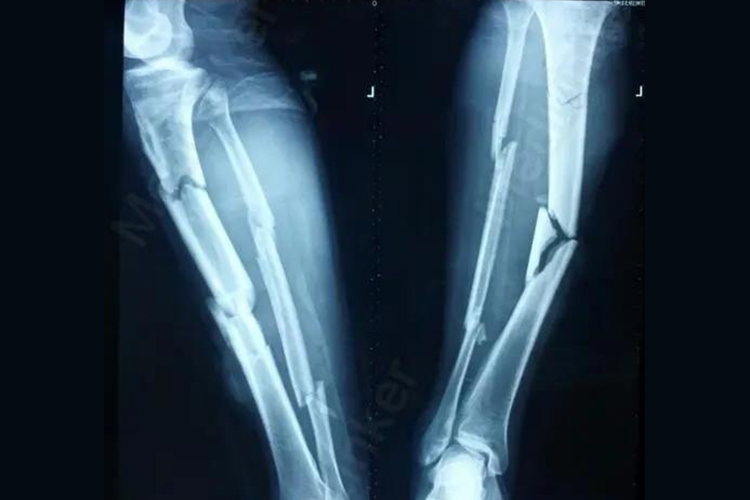

小腿粉碎性骨折主要是指小腿的胫腓骨发生骨折,影像检查可见胫腓骨的骨质碎裂成三块以上,同时可出现伤肢疼痛、肿胀、畸形等表现,当神经、血管受损,可导致足下垂,以及小腿皮肤的皮温、颜色改变,或足背动脉的搏动减弱或消失等症状。

小腿发生粉碎性骨折主要是由于胫腓骨遭受到高能量的暴力,如交通事故、工程事故等,导致胫腓骨受到强烈撞击、车轮碾压,可引起骨质破碎成三块以上,发生粉碎性骨折。

小腿粉碎性骨折属于不稳定性骨折,需及时采取手术方法进行治疗,可采用微创或切开复位,可选择钢板螺钉或髓内针固定。对于存在严重软组织损伤的开放性胫腓骨干双骨折,在进行彻底的清创术后,可选用髓内针或外固定架固定,同时作局部皮瓣或肌皮瓣转移覆盖创面,不使内固定物或骨质显露。